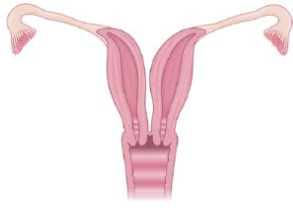

Utérus Bicorne